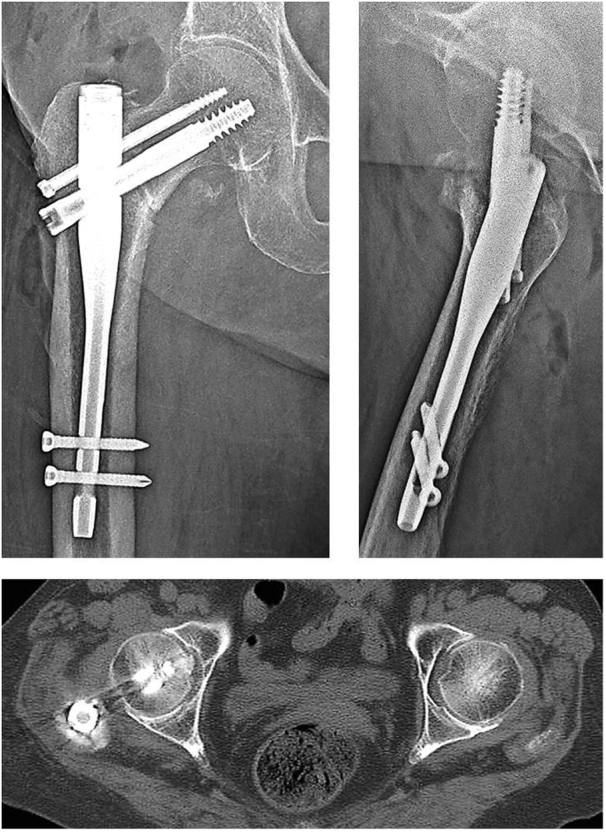

Fig. 3.

Reverse Z-effect phenomenon treated with cephalomedullary nail with two superior antirotation screws. The inferior lag screw has penetrated the femoral head into the acetabulum, and the superior antirotation screws have migrated laterally.